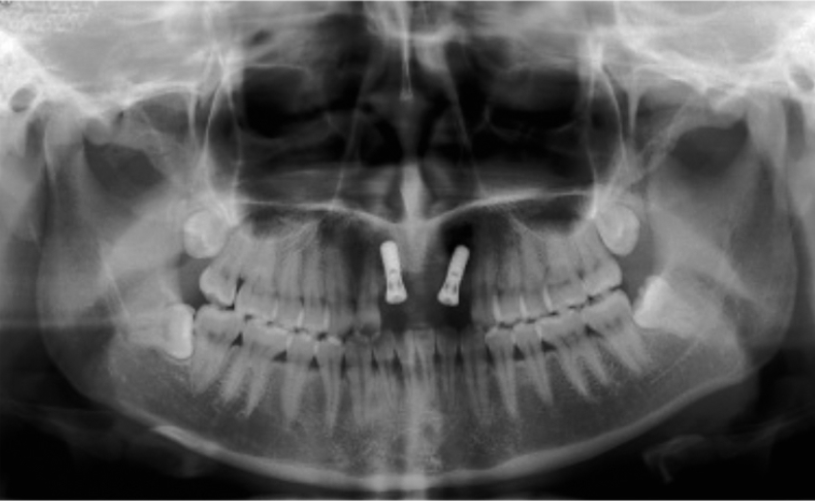

图1 术前全景片显示A1B2缺失

图2 术后全景片A1B2种植术后

首先在进行临床检查时,可以观察到缺牙区的宽度和厚度,用手指扪诊时前庭沟骨质没有明显的凹陷,这种情况可以拍摄牙片了解牙槽骨状况及与鼻腔的距离。由于牙片显示的范围有限,最好能够拍摄全景片了解邻近结构的情况,比如邻牙的情况、鼻腔底的距离,切牙孔的大小与位置等等。